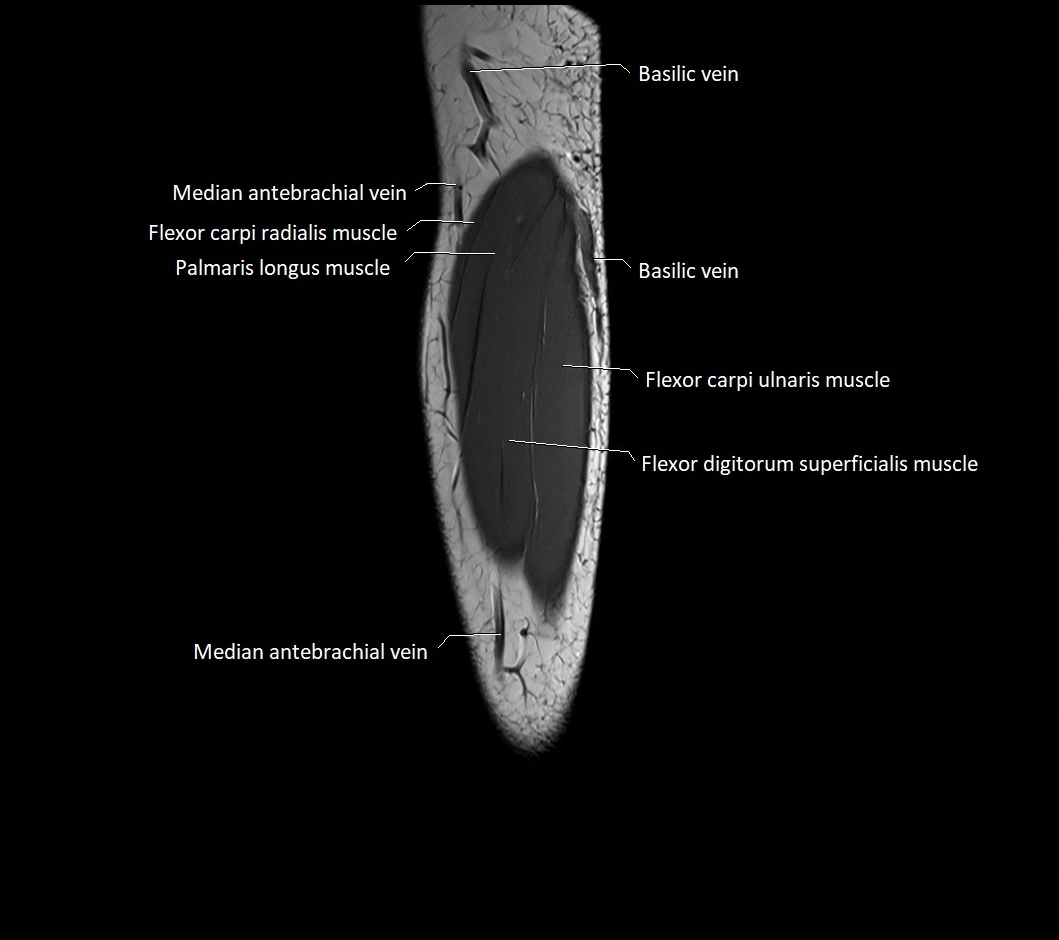

MRI images

image